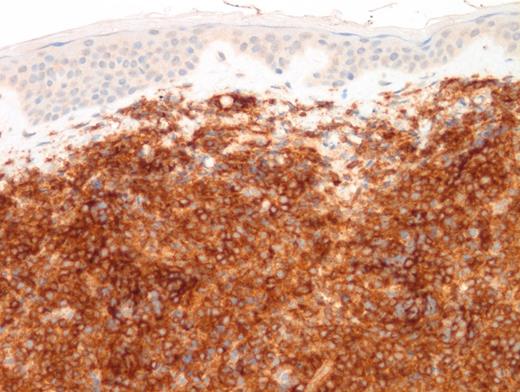

A 15-year-old girl presented with a three-month history of an erythematous rash on the medial side of the left breast. This was initially diagnosed as extramedullary myeloid tumor (EMMT). The patient received standard therapy for acute myeloid leukemia. Although bone marrow and cerebrospinal fluid analysis at the end of therapy showed no evidence of disease, there was cutaneous relapse in three months. An excisional skin biopsy was performed and showed an extensive/malignant appearing infiltrate involving dermis and underlying soft tissue and sparing epidermis and adnexal structures. Images of low- and high-power hematoxylin and eosin (H&E; Figures 1 and 2) as well as CD4 (Figure 3) and CD123 (Figure 4) immunostains are shown. In addition to these markers, a panel of immunostains revealed the dermal infiltrate to be positive for TdT, CD33, CD43, CD45, TCL1, TCF4, and CD68 KP1 (faint, focal).

TBPDCN is a rare, clinically aggressive neoplasm seen typically in adults. It has been rarely reported in the pediatric population. The disease tends to involve multiple sites, but skin is a common location. BPDCN is characterized by a monotonous infiltrate composed of undifferentiated medium-sized blastic cells with dispersed chromatin. The infiltrate spares epidermis and adnexal structures but extends deeply into the subcutaneous tissue. The typical immunophenotypic profile is CD4+, CD56+, and CD123+ neoplasm. However, a subset of cases (8%) are CD56-negative. An extensive panel of immunohistochemical stains (including TCL1A, CD303, and more recently, TCF4) further help to diagnose. Whenever possible, both flow cytometry and cytogenetics should be performed.

Differential diagnosis with EMMT is challenging,1 particularly in CD56-negative cases. In this case, the faint expression of CD68 (KP1) coupled with CD33 and CD43 expression was suggestive of EMMT. However, CD33 and CD43 positivity can be seen in both BPDCN and EMMT. Furthermore, CD4 is commonly expressed in myeloid sarcomas with monocytic differentiation, especially in NPM1-mutated cases. Diffuse positivity for CD123 in a CD4+/TdT+ malignant neoplasm should alert the pathologist for a diagnosis of BPDCN even in the absence of CD56. In this case, additional TCF4 and TCL1 were eventually performed and showed diffuse positivity. The former marker (TCF4) is a crucial marker expressed in blastic cells with differentiation towards PDCs and its positivity allows exclusion of myeloid lineage. Dual expression of TCF4 and CD123 was found to be sensitive and specific for BPDCN.2 The distinction is critical since pediatric BPDCN patients benefit from lymphoid-directed therapy. A novel CD-123 directed targeted therapy3 was also recently approved by the U.S. Food and Drug Administration for adults and pediatric patients with this disease.